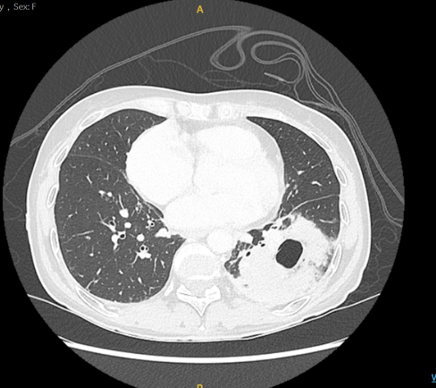

Il s’agit d’une patiente de 59 ans en bonne santé habituelle, sans comorbidité, qui se présente aux urgences suite à un malaise avec chute. Elle présente depuis quelques jours un syndrome grippal avec asthénie, état fébrile et toux. Depuis 2 jours, elle décrit également l’apparition d’une douleur abdominale avec quelques épisodes de diarrhées. Lors de ton examen clinique, la patiente est stable sur le plan hémodynamique mais présente une désaturation à 90% AA et une tachypnée à 25/minutes. Le laboratoire met en évidence un syndrome inflammatoire avec une CRP > 300 mg/dl, sans leucocytose, une hyponatrémie légère ainsi qu’une hypoxémie à la gazométrie. Sur le plan microbiologique, la PCR sur frottis nasopharyngé à la recherche d’une grippe Influenza A est positif, alors que les hémocultures et la culture d’expectorations restent stériles. Il n’y pas d’antigène à Legionella et pneumocoques dans les urines. La radiographie et le scanner thoracique ci-dessous mettent en évidence une lésion pulmonaire excavée.

Une lésion pulmonaire excavée est définie comme une opacité parenchymateuse pulmonaire avec en son sein une hyperclarté avec ou sans niveau hydroaérique et entourée d’une coque.

Lors de la mise en évidence d’une telle lésion à la radiographique, il est préconisé d’effectuer un CT thoracique afin d’orienter le diagnostic. Si l’origine est plutôt infectieuse, une antibiothérapie  d’épreuve peut être mise en place avec un CT de contrôle à distance. En cas d’absence de régression de la lésion excavée, il s’agira d’effectuer une endoscopie bronchique ou ponction trans-thoracique, avec ponction ganglionnaire pour établir un diagnostic histologique.

En ce qui concerne notre patiente, l’évolution clinique et scannographique a été favorable sous traitement de co-amoxiciline.